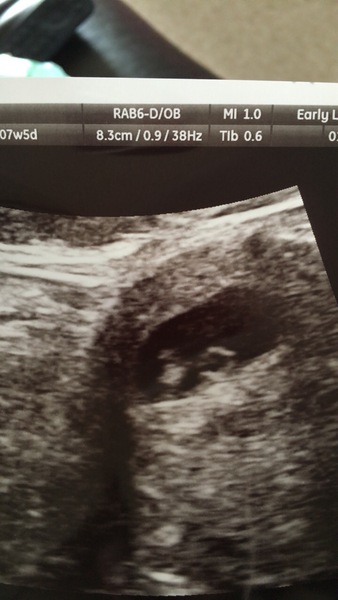

Not much to see on the pic but this is the best one I think.

I totally understand wanting to find out onyour own terms @Jessabean If I could justify the cost I’d have another scan between now and twelve weeks. I found out about the mmc when I started spotting at 11+3 last time and then miscarried naturally the night/morning before my second scan 10 days later. They were never exact but suggested the baby had stopped developing somewhere between 6 and 7 weeks. I found the physical process traumatic and ended up in a&e. I’m terrified of going through that again.